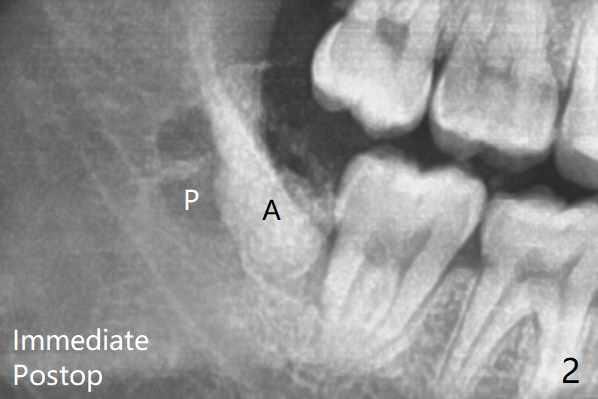

A 23-year-old man with poor oral hygiene presents to clinic with pain at #1 and 32.  Because of bone loss between #31 and 32 (Fig.1 *), Bond Apatite (1 cc, Fig.2 A) is placed in the defect area following insertion of Collagen Plug in the sockets (P, a half).  The other half of the Plug is placed coronal to Bond Apatite before suturing with 4-0 PGA.